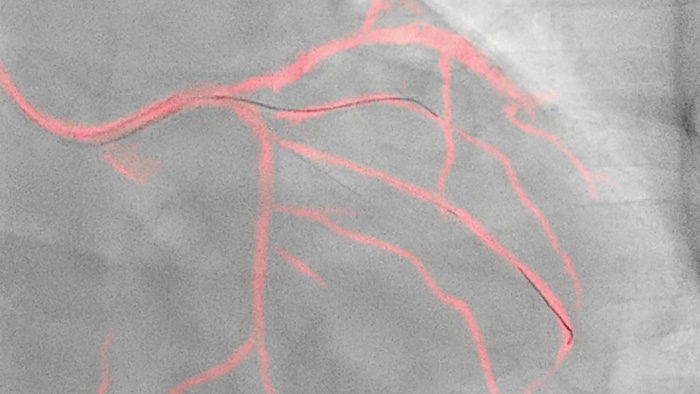

フィリップスの技術により、冠動脈の体動補正されたリアルタイムビューを作成します。ハイライト表示された冠動脈造影画像がライブ2D透視画像に重ねて表示され、カラーロードマップが作成、自動調整され、ワイヤやカテーテルの配置に関する連続的な視覚的フィードバックが提供されます。